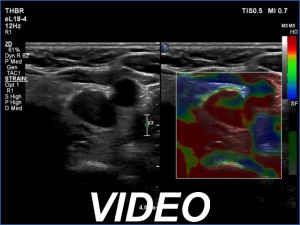

Ultrasonography. The thyroid was atrophic and hypoechoic. There was a hypoechoic mass under the lower pole of the left lobe.

Histopathology disclosed parathyroid adenoma.